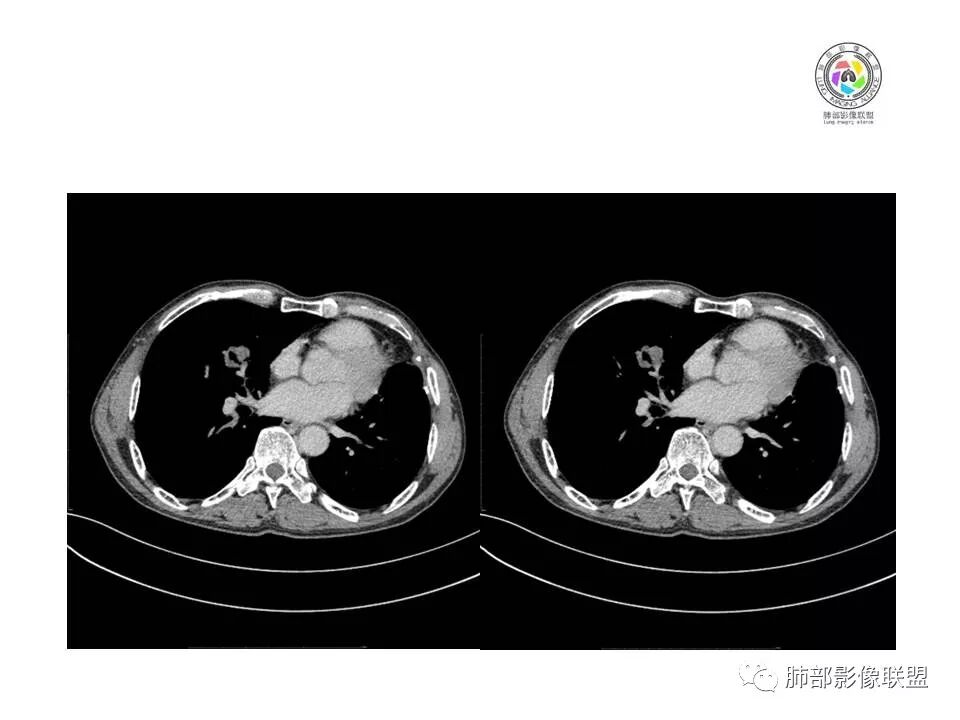

患者老年男性,间断咳嗽、咳痰伴痰中带血2个半月就诊,胸CT:右肺中叶内侧段占位性病变,病变可见分叶,周围可见结节影。病灶内可见厚壁空洞,洞壁光滑,未见洞壁结节,右肺中叶内侧段近肺门处支气管壁增厚。诊断:考虑结核,鉴别:肺癌,建议痰找抗酸杆菌、支气管镜检查

老年人,右肺中叶內侧段结节病灶,内见不规则空洞,近端可见引流支气管,其支气管壁增厚。结节病灶周围可见卫星灶,考虑肉芽肿病变,结核可能。

老年男性,肺气肿背景,右肺中叶结节,边缘膨隆,有分叶及细毛刺,厚壁空洞,考虑恶性,腺癌。

老年男性,咳嗽痰血,影像:肺气肿背景,右肺中叶结节,分叶膨隆为主,部分平直,空洞,内壁光滑,壁厚,未见索条?树芽征、引流支气管,考虑恶性,男性、肺气肿、小病灶空洞鳞癌可能性大,需要与TB鉴别。

右肺中叶内侧段实性病灶,病变可见深分叶,棘突,毛刺,周围多发结节影。病灶内可见厚壁空洞,内壁光滑,未见壁结节,增强轻度强化,右中叶内侧段支气管壁增厚。诊断:肉芽肿性病变,结核?隐球?鉴别:肺癌

晨读,老年男性,肺气肿背景,右肺中叶结节,边缘膨隆可见分叶,边缘毛糙,内可见小空洞,强化后呈轻度强化,可见血管影,首先考虑肺癌,建议支气管镜检查,除外结核。

晨读,有个问题,左肺体积减小?纵隔左移,右肺代偿?左肺有没有手术史?假如是癌手术,要考虑转移的问题。影像,右肺中叶不规则分叶结节,支气管开口通畅,门口到肿块中间堵塞,到肿块近边缘又能看见走形,有毛刺,内沙砾样钙化,强化给的是延迟期,轻度强化或无强化,考虑恶性。需要鉴别结核。

晨读:几个征象的认定,1.是空洞还是空腔?未见明确与支气管相通,空洞/空腔形态不规则,内部光滑;2. 有血管穿行?见血管影穿过无明显破坏;3.有没有强化?没给出平扫,猜测有轻度强化、较均匀;3.分叶、毛刺均有;总体判断:MT可能大,其内为空腔而非空洞、加之有血管穿行,考虑为生长速度快包绕所致,不首先考虑鳞癌,以小细胞癌或腺癌可能。

晨读病例:患者老年男性,间断咳嗽、咳痰伴痰中带血2月余。实验室检查无明显异常升高。胸部CT:肺气肿背景,右肺中叶内侧段占位,密度不均,见分叶,边缘膨隆,部分可见边缘平直,支气管部分变窄、部分扩张,增强轻度强化,内可见低密度灶。综合考虑良性病变可能大,结核首先考虑,鳞癌待排。

老年男性,肺气肿背景,间断咳嗽、咳痰伴痰中带血2个半月,右肺中叶结节,边缘部分膨隆,部分平直,有小结节堆积感,中间空洞不规则,近端引流支气管扩张,壁增厚,这样的改变有三个可能,腺癌,鳞癌,结核,但小于3cm的腺癌一般不形成坏死空洞,更不会与支气管相通出现咳痰咳血症状,鳞癌小于3cm未经治疗也一般不与支气管相通,除非囊腔型鳞癌,但这个周围不是硬壳样改变。所以考虑结核可能。

晨读病例:老年男性,咳嗽痰中带血俩月,肺气肿背景,右肺中叶不规则结节影,有分叶,内有空洞还是扩张支气管?不均匀轻度强化,内有血管进入。考虑恶性肿瘤,鳞癌?

晨读:患者男性,68岁,间断咳嗽,咳痰伴痰中带血2个月。CEA轻度升高。肺气肿背景。左侧胸廓塌陷欠对称,右肺中叶结节,边缘膨隆有浅分叶,支气管未见明确鼠尾样截断,结节內似有点状偏高密度影,结节内是小空洞?还是扩张的支气管?结节周围未见卫星灶。叶间裂无牵拉,收缩不明显。腺癌放后吧,在鳞癌和结核之间鉴别,肯定建议支气管镜检查。考虑恶性,猜个鳞癌。

良恶性征象都有,恶性征象多于良性,空洞呈偏心,壁厚薄不均,首选恶性,TB放后。

老年男性,咳嗽痰血,肺气肿,右肺中叶结节,分叶膨隆为主,部分平直,空洞,内壁光滑,壁厚,轻度强化,考虑恶性,鳞癌?与TB鉴别。